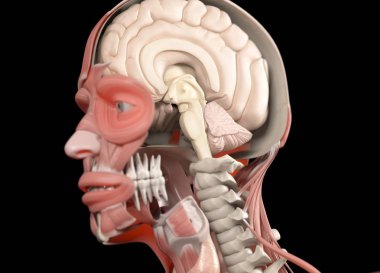

The arterial blood supply to the neck (carotids and vertebral arteries).

İnsanBaşıkanİlaçyüzboğazıBoyunresim çalışmasıprofilNormalbeyinarterkarotidKan damarıKan dolaşımıİnsan AnatomisiSerebral kan dolaşımıvaskülarizasyonsubclavian arteryortak Karotis arterbrachiocephalic Arteryel gövdeVertebral arterfacial arteryserebral artercervical arterytemporal arterydahili şah damarıharici şah damarıdeep cervical arteryBenzer İçerikler